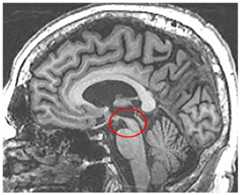

Neuroimaging

Structural imaging in PSP may reveal midbrain atrophy referred to as the hummingbird sign on sagittal images (Figure 5-629), as well as hypometabolism in frontal, caudate, midbrain, and thalamic regions on FDG-PET.30

Figure 5-6.

Midbrain atrophy in progressive supranuclear palsy. Midsagittal MRI in a patient with progressive supranuclear palsy demonstrating thinning of the rostral midbrain resulting in the hummingbird sign.

Modified with permission from Boeve B, Parkinsonism Relat Disord.29www.sciencedirect.com/science/article/pii/S1353802011700608. © 2011 Elsevier Ltd.